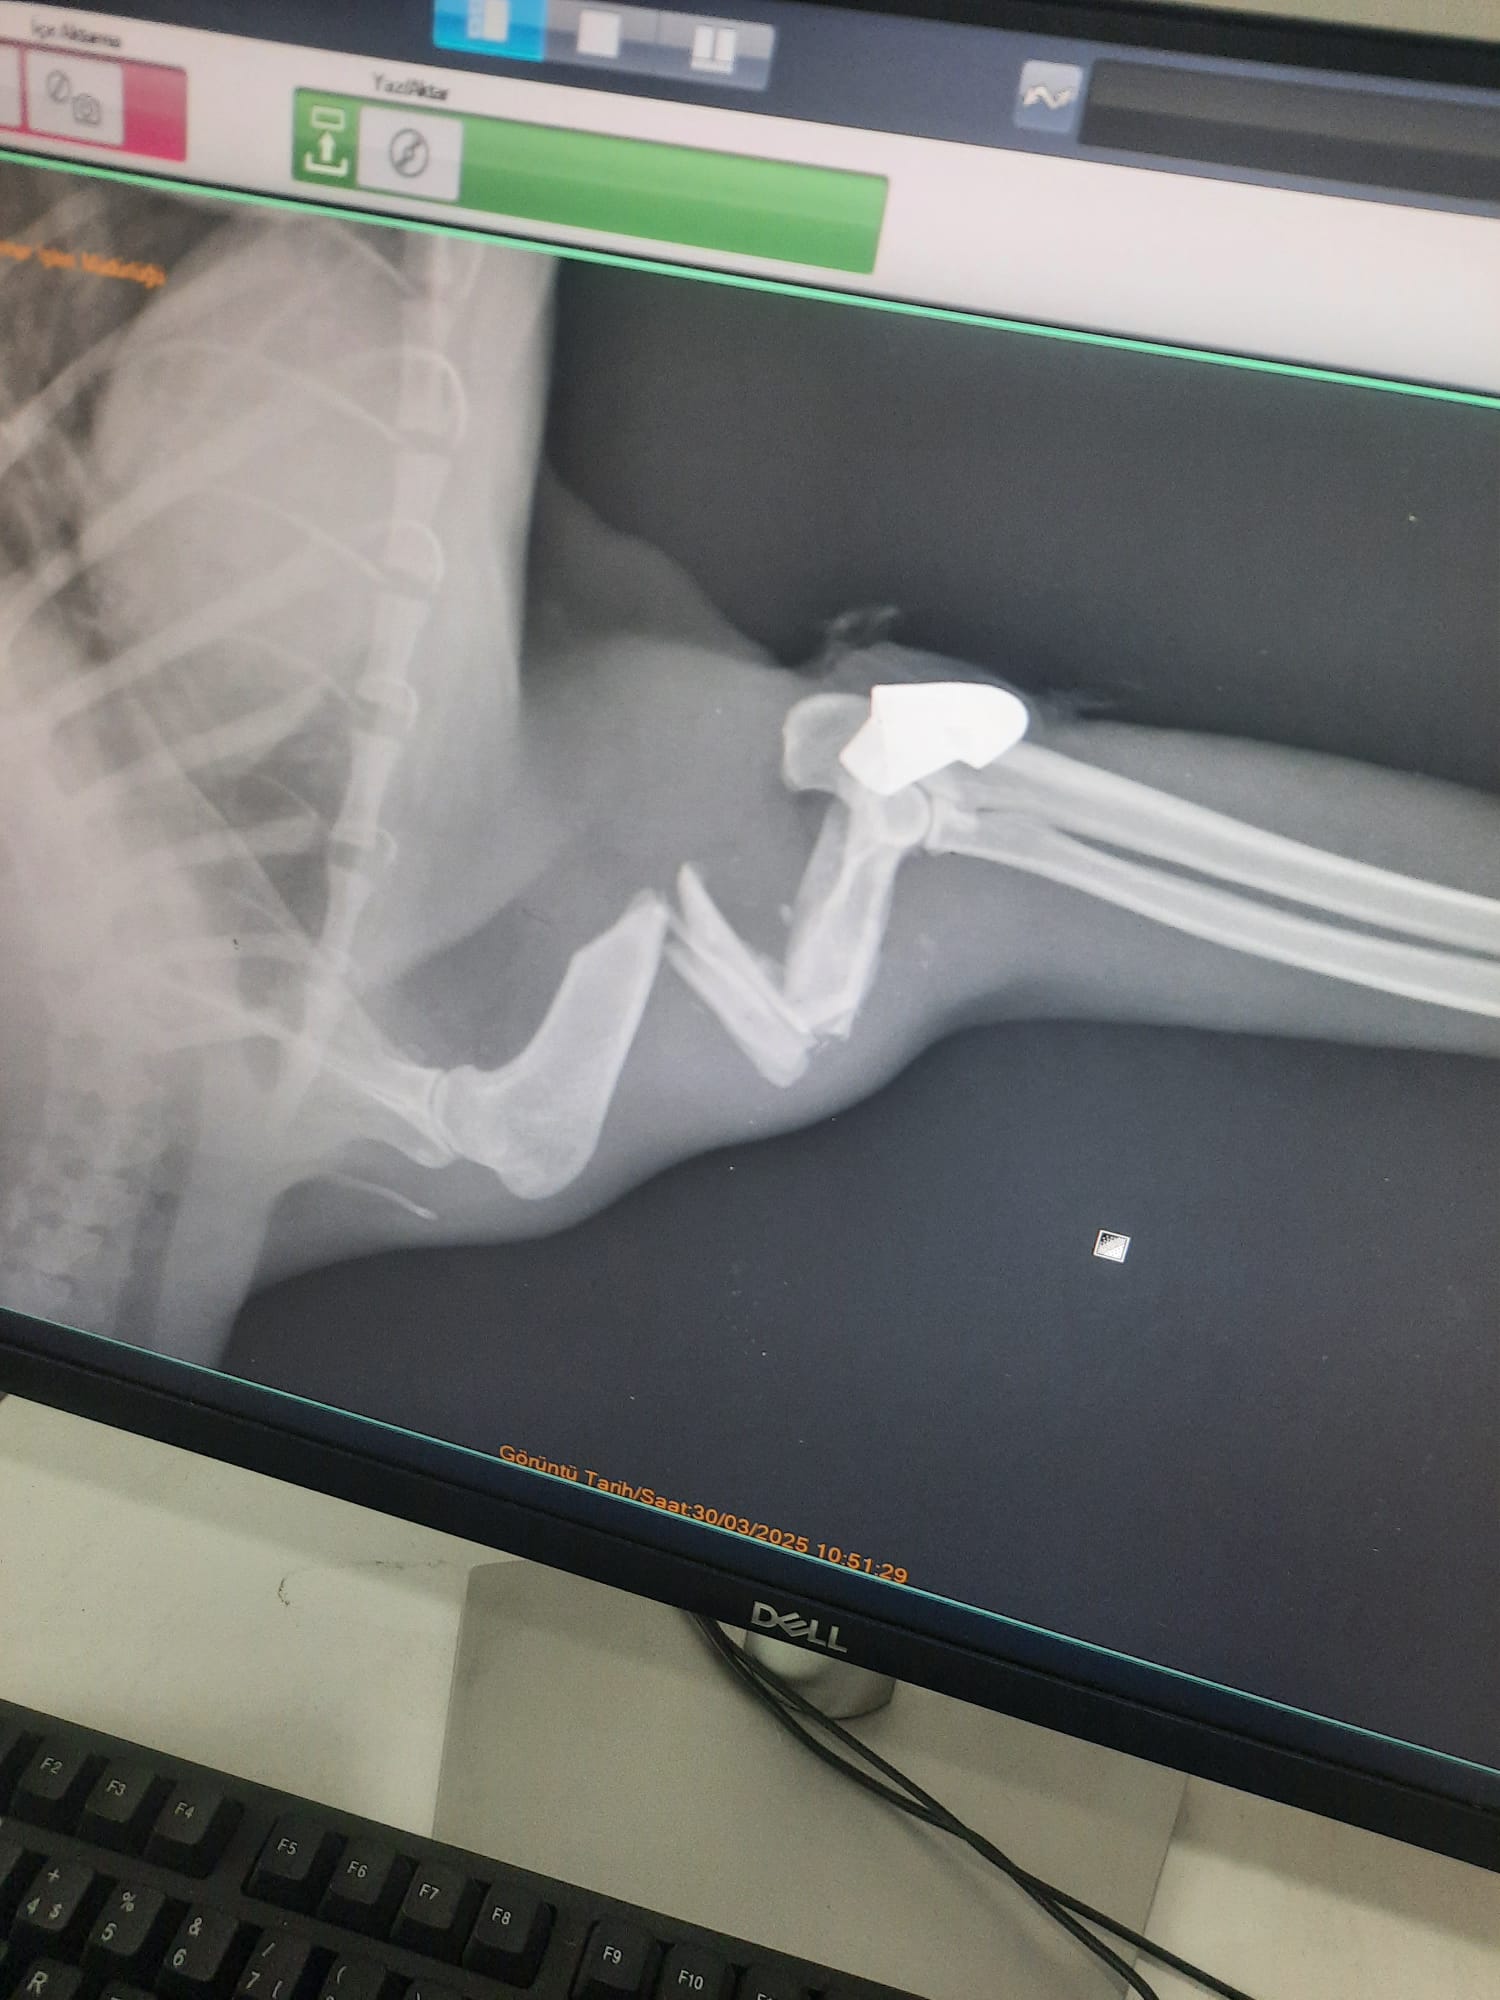

Zonguldak Kilimli ilçesinde, Seda Özkaya’nın baktığı sokak kedisi, bundan 2 ay önce birden bire kayboldu. Özkaya, kedisinin patisinin üstüne basamadığını fark etti. Tedavi için Zonguldak Belediyesi Veteriner İşleri Müdürlüğü’ne götürülen kediye röntgen çekilince patisinde mermi olduğu görüldü.

Mermi ameliyatla çıkarıldı. Zonguldak Belediyesi Veteriner İşleri Müdürü Rıza Akçay, “Röntgenlerini falan çektik. Sonuç olarak, ameliyatını yaptık. Ameliyat başarılı geçti. Eski sağlığına inşallah kavuşacak. Yorgun mermi isabet etmiş. Çekirdeği zaten üzerindeydi. Onun için diyoruz zaten yorgun mermi. Gerekeni yaptık” dedi.